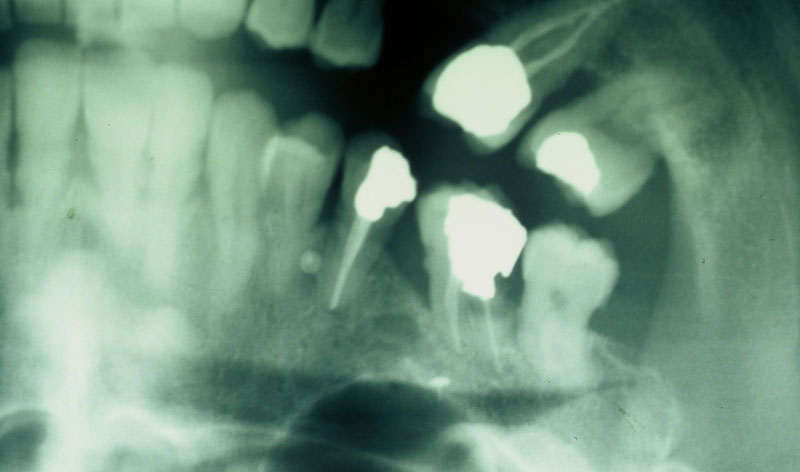

Es una intervención sencilla, que se asocia a la colocación del implante en los casos en los que el hueso no es lo suficientemente ancho como para que el implante quede rodeado por el mismo en su totalidad.

En algunos casos se regenera en el momento de la extracción del diente, para preparar mejor el hueso, dejándolo cicatrizar durante un tiempo hasta la puesta del implante. En otros, es en el momento de la colocación del implante cuando recurrimos a la regeneración del hueso perdido.